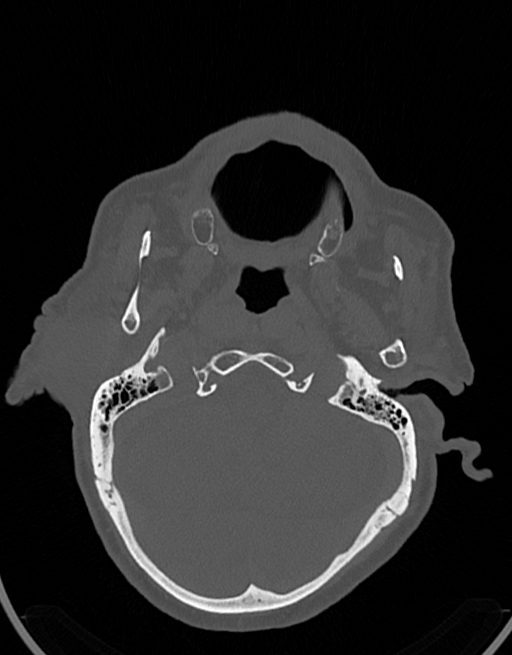

در سي تي اسکن اسپيرال نازو فارنکس با و بدون کنتراست (مولتي ديدکتور 16 با مقاطع ظريف و بازسازي هاي ساژيتال و کرونال):

– توده نسج نرمي به ابعاد mm 40 x 45 x 60 در ناحيه پاروتيد راست، با enhancement هتروژن پس از تزريق کنتراست مشهود است که مطرح کننده آدنوم پاروتيد مي باشد.

– شواهدي از تهاجم توده به استخوان و عروق اطراف مشهود نيست .

– کلسيفيکاسيون در ديواره شريان هاي کاروتيد دو طرف مشهود است .